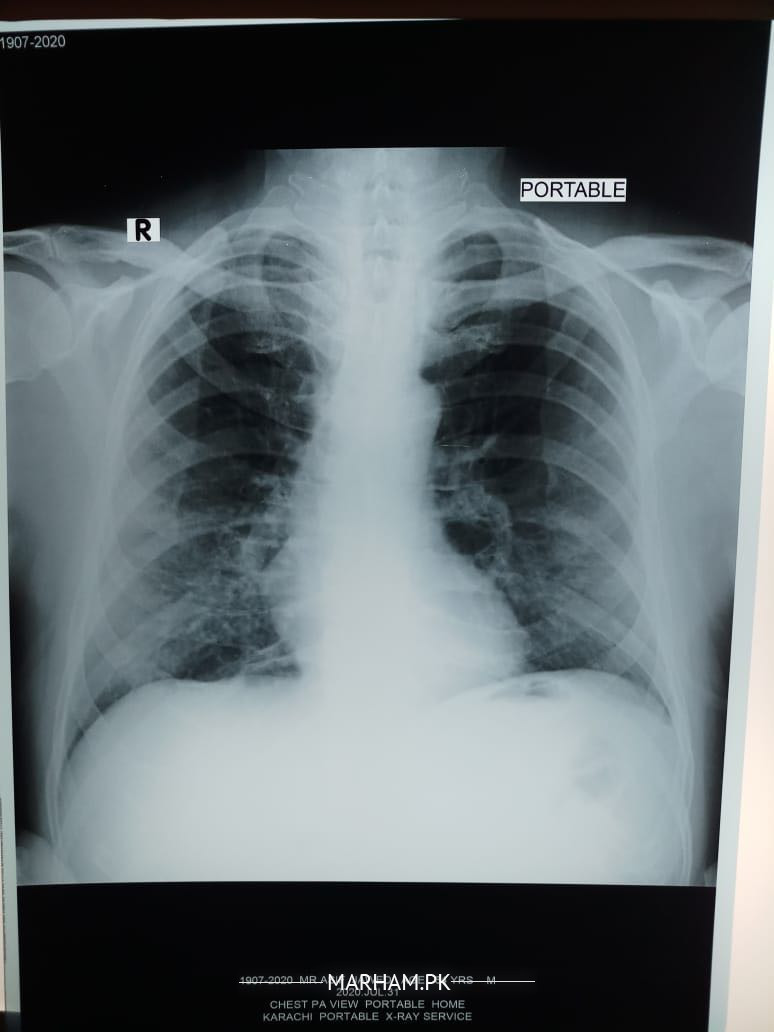

My father tested positive for corona yesterday. He has had fever 100 101, severe weakness and cough, loss of appetite etc. We got a chest extant done today and the radiologist’s report says this “â€Fibro nodulations both mid and lower zones. Rest of the lungs are clear . Cardiac size within normal limits . No evident of pleural effusion. Costophrenic angles are clear . Bony cage is intact . Conclusion. Bilateral pulmonary infection “â€. Pls advice what can be done should he be taken to the hospital?

dear the findings in x ray can be due to corona virus infection

but they can also be due to other causes

Shortness of breath no I don’t know for sure although when he speaks he starts panting and coughing after a few sentences. He’s diabetic and hypertensive both with arthritis. This is today’s xray

Can anyone pls explain what the X-ray shows? He started antibiotic on Saturday. Azomax 500 once daily with Panadol x 2 thrice a day